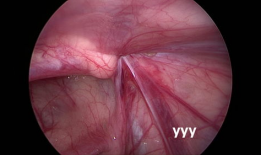

疝气手术视频,从术前准备到术后恢复

你有没有想过,当你在网上搜索“疝气手术视频”时,会出现什么样的画面呢?今天,就让我带你一起揭开这个神秘的面纱,看看那些让人既好奇...

2025-08-16 98 -